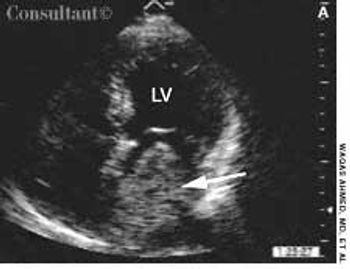

For 2 years, a 60-year-old woman with long-standing hypertension had experienced worsening dizzy spells, fatigue, and chest discomfort. She also had cold extremities, significant dyspnea on exertion, and orthopnea. The patient was taking amlodipine and furosemide.